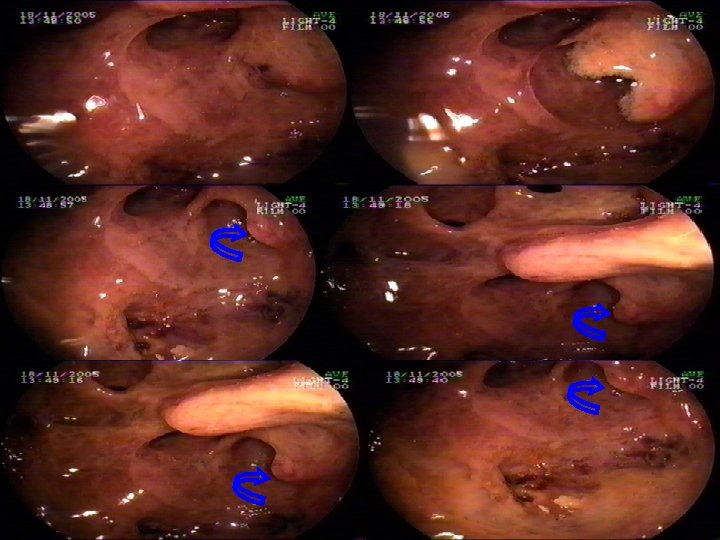

n n n CASO 1. PAC M. V. ICTERICIA EN ESTUDIO Paciente. Visitador Medico de 39 años de edad, quien consulta desde hace un año en diferentes Clínicas , interpretando el cuadro como un Trastorno funcional, con: 1. - Meteorismo Progresivo. 2. - Diarrea crónica. 3. - Colicos en Epigastrio e HD en 7 oportunidades dentro de un año, manejándose con antiespasmódicos y medicamentos para el colon. 4. - Intolerancia Progresiva a alimentos grasos, 5. - Aparece cuadro de Depresión y gran ansiedad, deteriorando su relación familiar. 6. - Finalmente, aparece Ictericia de Piel y Escleras con Coluria y esteatorrea. 7. - Aumento progresivo en Patrón colestásico, con niveles bilirrubina sobre 50 8. - Baja de peso mayor a 10 kg en 3 meses Posteriormente se hospitaliza solicitandose nuevamente Colangioresonancia y EUS terapeutico los cuales revelan pancreatitis crónica con elementos de reagudizacion y quistes intra y peripapilares, con papila deformada. Aqui el paciente es sometido a la permeabilización por via MIXTA ENDOSCOPICA Y PERCUTANEA de la via biliar intrahepatica. n El paciente es sometido posteriormente a amputacion de la papila. Dentro de esta Cirugía Endoscópica se corrobora la aparición de tejido gelatinoso, concluyéndose ciatoadenoma Mucinoso peripapilar, sin infiltración sólo con alteración estructural propia de un páncreas con daño crónico. Todo lo anterior, determina un drenaje oportuno del paciente especialmente luego de la colocacion en un tiempo de protesis biliares y pancreaticas. El tiempo de hospitalizacion fue de dos semanas, dándose de alta posteriormente para integrarse a sus actividades Profesionales habituales, controles periódicos del area resecada, la cual regeneró al de una papila plana.

TECNICA UTILIZADA: RESECCION ENDOSCOPICA Nov. 2003 HTC MEDIANTE EUS (EN DOS TIEMPOS). Paciente: Sr. Mario V. V. 39 39 años Diagnostico 01: Ictericia Obstr, 66 meses evolución, CEG, Estenosis Colédoco Distal por Obs Neo Páncreas. US, CT, RM, Colangio. RM(2 Centros), Punción Percutánea Hepática. Tumor peripapilar Estómago Dgco post EUS: Lesión Quística Papila-Cabeza Páncreas (+) Pancreatitis ag. Tto: Apertura con Pre-cut yy Resección Papilar con Técnica de de Resección en en “Gajos Naranja” de de 33 lesiones quísticas adheridas aa paredes de de la la Papila. Tumor Papilar Colédoco Duodeno Conducto Wirsung Costo EUS (+)Cirugía Endoscópica, esfinterotomía, prótesis naso biliars: $$ 1, 500, 000, - Conducta Posterior: Segundo Tiempo EUS para corroborar ausencia Neo, con raspado de de lecho pancreático, con Bps (-) previa consulta grupo Brasil 15 15 días después: $ 150, 000, Páncreas Costo Paciente(Incluída hospitalización yy medicamentos): $$ 4. 902. 893, Cirugía Tradicional: Resección abierta con operación de de Whipple Costo; $$ Morbimortalidad resección EUS == 4 -12% Morbimortalidad resección Quirúrgica == 30%